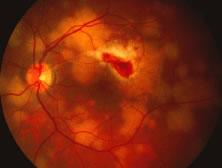

The ARN patient typically presents with progressive visual blurring in one or both eyes occurring over several weeks. These patients often are initially treated with corticosteroids, antitoxoplasmosis drugs, and other medications before arriving at the correct diagnosis. Examination reveals a prominent anterior uveitis that may be granulomatous or nongranulomatous (Fig. 1). Inflammatory signs may be prominent and cause severe pain (Fig. 2). The uveitis may be diffuse and so severe that it causes proptosis. These signs, and the diffuse vitreitis that makes the view of the retina difficult, may contribute to the high degree of delayed and/or misdiagnosis that occurs in the early stages of the disease. Significant vitreous cellular infiltration is seen in the presence of retinitis that is manifest by opacification of the retina, often most prominently in the periphery. Posterior pole involvement may include retinitis, as well as inflammation of the optic nerve head. Optic neuropathy might be the first sign of ARN with subsequent development of other retinal manifestations.8 Ultrasonography and computed tomography (CT) might be helpful in cases of ARN associated with optic nerve edema revealing enlargement of the optic nerve sheath.9 Even in ARN patients who are not immunocompromised and who have no clinical evidence of encephalitis, magnetic resonance imaging of selected cases has shown lesions of the lateral geniculate, optic tracts, and chiasma, which suggests that the virus spreads through the central nervous system (CNS) by axoplasmic transport from the retinal ganglion cells.10 A secondary retinal vasculitis is common, often accompanied by a mild number of retinal hemorrhages. Days to weeks after onset of the infection, the discrete peripheral lesions typically coalesce into a white or yellow ring of infected retina, and the associated vasculature is obliterated (Fig. 3). Necrotic retina desquamates into the vitreous resulting in vitreous sheets.3,6 Eventually, most untreated eyes can be expected to develop retinal detachment resulting from development of multiple full-thickness retinal breaks accompanied by traction or exudation.11 Giant retinal pigment epithelial tears have also been reported.12